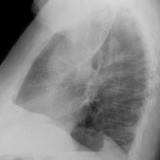

LUL Collapse Case 1 Lateral